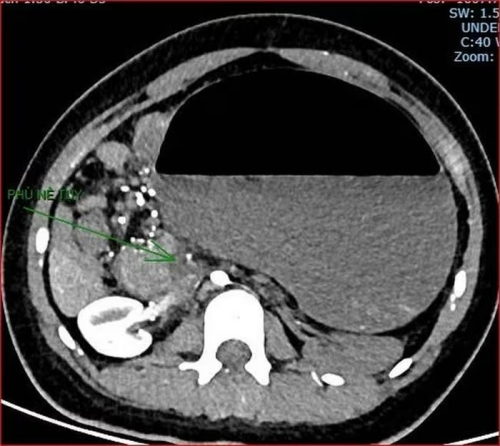

Khoảng 21h40, kết quả chụp CT cho thấy bệnh nhân rơi vào tình trạng cực kỳ nặng và hiếm gặp, bao gồm: Xoắn dạ dày, nhồi máu thận trái, nhồi máu lách, viêm đầu tụy, viêm hỗng tràng, kèm dịch ổ bụng và tràn dịch màng phổi, trên nền bệnh nhân mắc hội chứng Down và tim bẩm sinh.

Kết quả chụp CT cho thấy bệnh nhân rơi vào tình trạng cực kỳ nặng và hiếm gặp. |